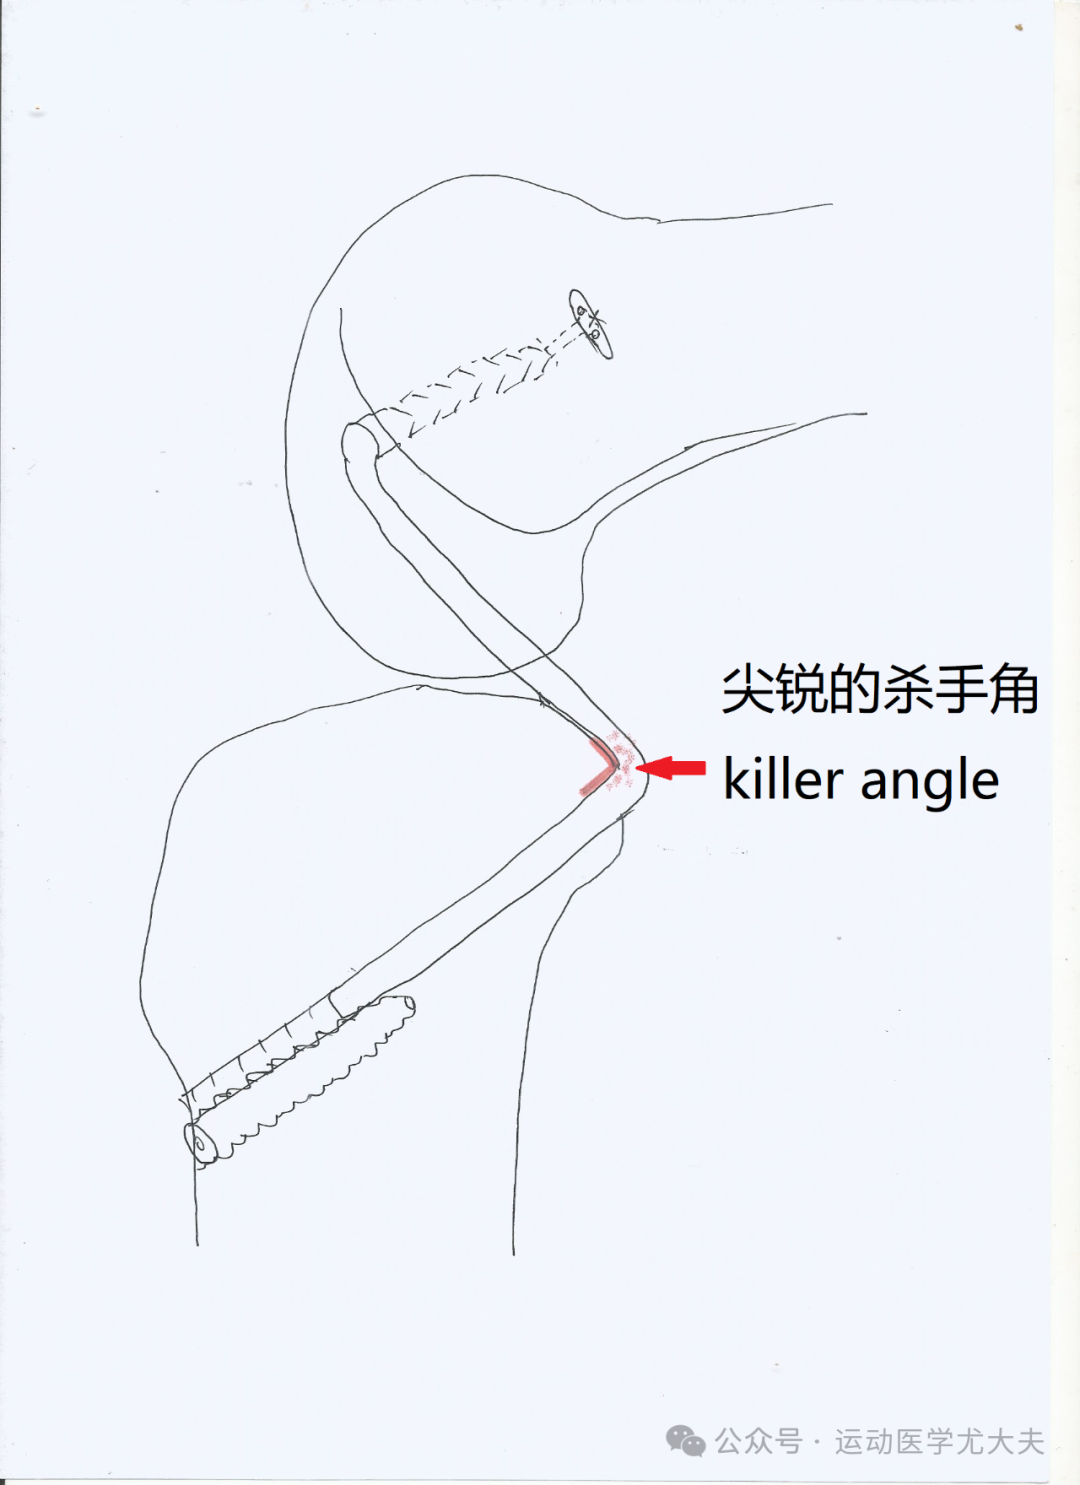

如何预防后交叉韧带术后松弛的发生?解决可怕的杀手角(killer turn / killer angle)

后交叉韧带重建(PCLR)术后往往难以长久保持膝关节原有的后方稳定性,术后膝关节渐进性后方松弛的问题一直是PCLR术后的难题。无论应用何种类型移植物(自体肌腱/人工韧带)、采取何种手术重建方式(单束/双束),术后残留膝关节后方松弛的现象屡见不鲜,后移3mm以上的松弛率为22%~54%。根据国际膝关节文献委员会(IKDC)的定义,后抽屉试验的松弛度可分为0级(后移0~2mm)、Ⅰ级(后移3~5 mm)、Ⅱ级(后移6~10 mm)、Ⅲ级(后移 > 10 mm)。虽然这种1-2度的松弛不一定会有临床症状,但仍然会引发膝关节异常的运动学表现,而且持续的后方松弛,更可能导致患侧膝关节半月板损伤、软骨退变,最终导致膝关节骨关节炎的发生。PCL重建术后膝关节后方松弛残留的主要原因包括:杀手转弯角效应(killer turn / killer angle)、股骨骨隧道定位不佳、胫骨平台后倾角过小及术后康复不合理等。其中,杀手角是最为明确的、影响最大的,同时也是研究得最多的有害因素。Bergfeld等(Bergfeld JA, et al. AJSM. 2001)的尸体标本测试发现:在屈伸膝2000个循环后,杀手角处的移植物的厚度会损失将近一半(40.6%),进而会被拉长9.8mm。我国已故的运动医学大咖冯华教授的团队(Li Y, et al. Asia Pac J Sports Med Arthrosc Rehabil Technol. 2016)则在兔标本中发现:在屈伸膝1500个循环后,除了移植物会拉长5.59%±4.98%,在反作用力的影响下,胫骨隧道的内口直径也会扩大12.08%±4.31%,移植物的磨损和隧道内口的扩大呈线性正相关,二者共同导致后方松弛。虽然我们不能解决所有影响PCLR术后松弛的问题,但杀手角这种具有明确意义的,同时也易于在术中控制的因素,还是应该努力避免,解决起来也很简单,尽量将胫骨隧道的内口下移就行,当然,这就要求我们制备更长的移植物,通常需要长1-2cm,如果单侧的腘绳肌腱不够,则加用对侧腘绳肌腱或者同侧腓骨长肌腱,又或者是通用人工韧带。图3. 术前的后交叉韧带陈旧损伤,松弛明显,探钩可轻易挑起图4. 重建好的后交叉韧带,屈伸活动完全等长,膝关节恢复稳定图6. 如此,我们便获得了一个圆滑的杀手角,可以有效地保护移植物昨日该病友已经顺利转入康复科继续治疗,愿这位美女早日痊愈,也祝大家新年快乐!